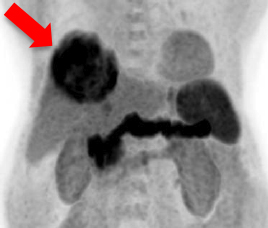

Pre-treatment Dual-tracer PET/CT

1. Identify metabolic heterogeneity factor

2. Classify cellular differentiation

3. Delineate radiosensitivities

- Liver tumor is inoperable because of its high metabolism and large size

- AFP is 2269 ng/ml

C-11 Acetate F-18 FDG